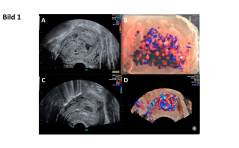

Im Bild: Uterine arterio-venöse Malformationen: eine Fallserie aus Bern

Wie bereits im erschienenen Beitrag „Plazentapolypen und andere vaskuläre, uterine Tumoren“ der FHA 2/18 beschrieben, stellen arterio-venöse Malformationen (AVM) eine wichtige Differentialdiagnose der uterinen Gefässtumoren dar [1]. PDF Dokument